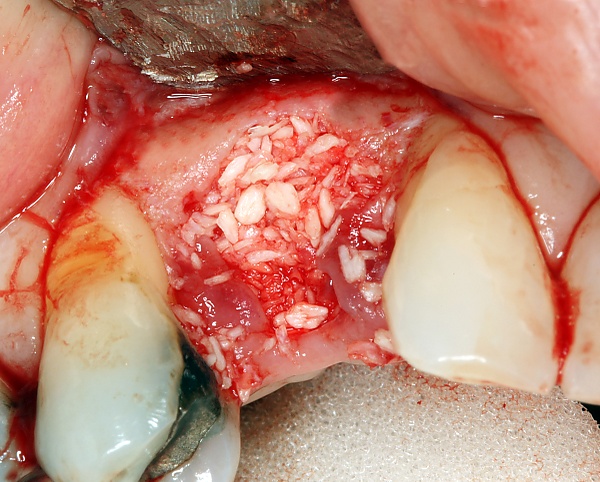

Разборный имплантат состоит из непосредственно имплантата и надстройки (супраструктуры), именуемой абатментом. Такой имплантат может быть установлен по одно- и двухэтапному протоколу. Двухэтапный протокол подразумевает полное погружение имплантата и накрывание его слизистой оболочкой, в результате чего исключается любой контакт имплантата с полостью рта — эта процедура называется первым этапом дентальной имплантации. Второй этап заключается в установке какой-либо надстройки (супраструктуры) — это может быть как формирователь десны, так и абатмент с временной коронкой или другим видом протезной конструкции. После какого промежутка времени будет выполнен второй этап обычно решает имплантолог, опираясь на данные о качестве костной ткани, возраст и общее состояние пациента, а также свой клинический опыт. Классические сроки составляют 4—6 месяцев, однако последнее время существует тенденция к сокращению сроков ожидания до 2,5—3 месяцев. Это связано с лучшим пониманием процесса остеоинтеграции, а также оптимизацией макродизайна и микрохарактеристик поверхности имплантатов.

- успешно интегрироваться, не вызывать угнетения остеоинтеграции, а возможно и потенцировать её. Этому способствует высокая степень очистки от механических частиц и уровень стерилизации.